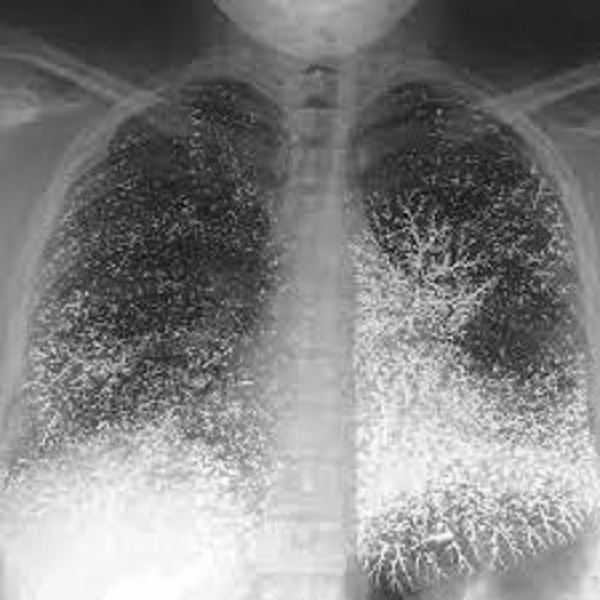

Ngay sau đó, các chuyên gia đã tiến hành mở cỗ quan tài ra và thực hiện 1 cuộc kiểm tra thân phận, cũng như nguyên nhân qua đời của chủ nhân ngôi mộ này bằng sóng điện từ.

Kết quả thu được khiến ai cũng sửng sốt, các bộ phận trên thân thể của chủ nhân ngôi mộ như phần đầu, não bộ, phần ổ bụng hay phần tay đều hiện rõ lên những vùng màu đen và những chấm đen dày đặc. Đặc biệt tại 3 vùng như bụng, tay và xương đều phát hiện 1 lượng lớn thủy ngân.